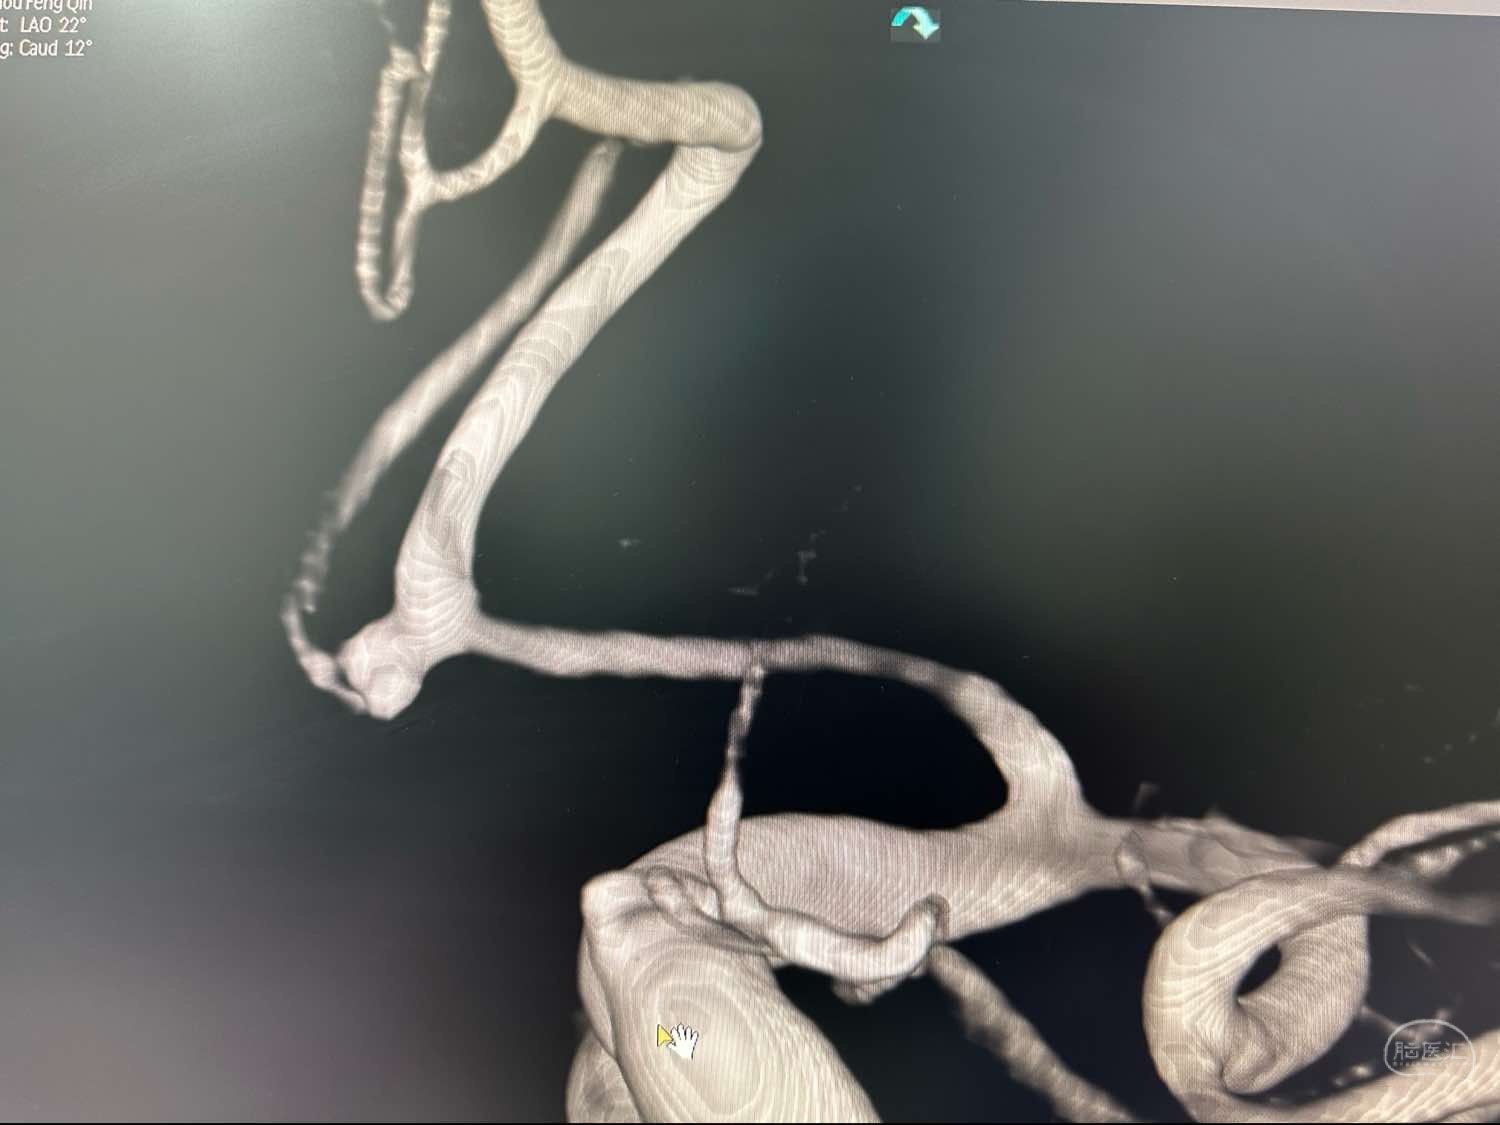

左侧颈内动脉造影3D